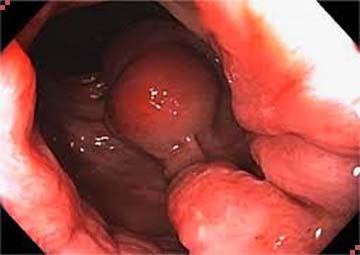

Hình ảnh trĩ nội độ 1

- Trong ống hậu môn có búi trĩ: Các búi trĩ nằm dọc trên đường lược phía bên trong ống hậu môn. Tuy chỉ nhỏ vừa bằng hạt gạo hoặc hạt đỗ nhưng tốc độ phát triển là rất nhanh.